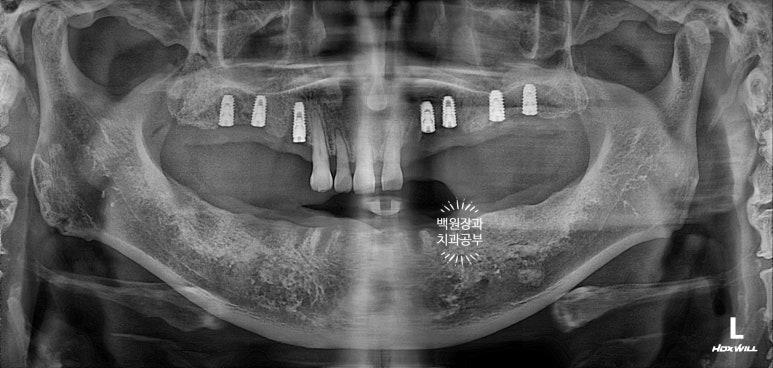

위턱 임플란트 수술 직후 파노라마 엑스레이 사진입니다.

처음 오셨을 때 갖고 계셨던 치아 중 흔들리지 않고, 비교적 제 위치를 잘 유지하고 있던 위턱 앞니 네개만 남겨놓았었네요...

건강한 사람은 위턱치아 14개, 아래턱치아 14개 총 28개의 치아를 갖고 살아갑니다.

그를 위해 위턱에 총 7개의 임플란트를 심어드렸었네요.